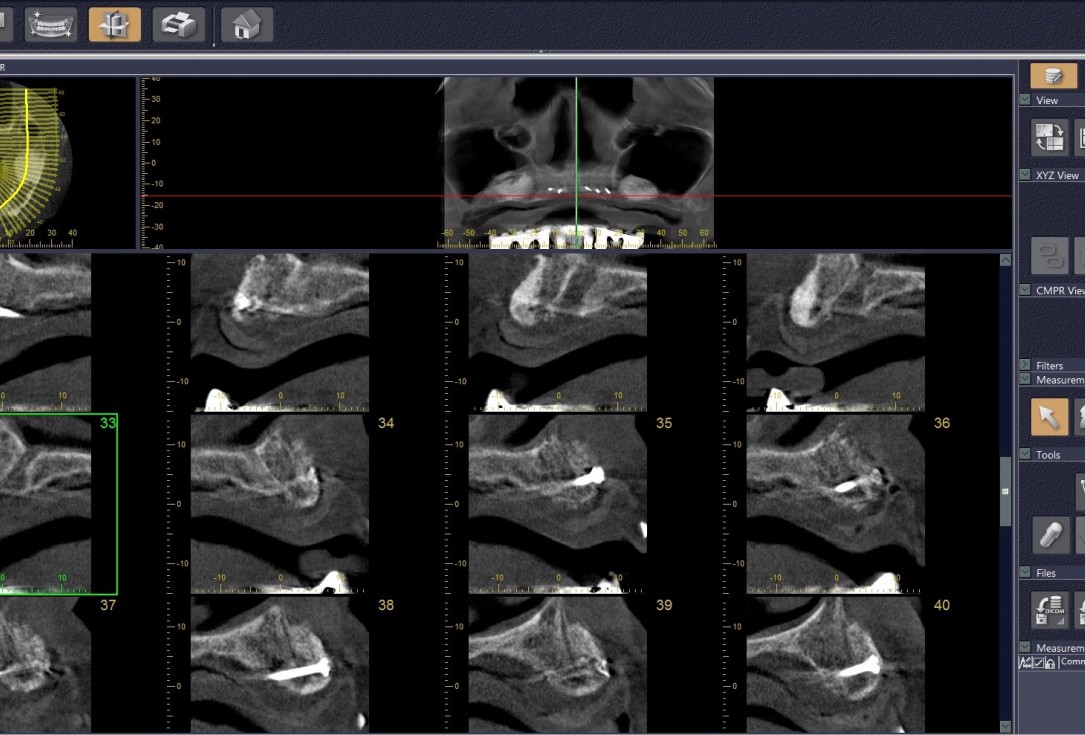

17/21 - CT scan 6 months post-op: Stable bone with Ø 8mm width

Reconstruction of maxillary ridge with maxgraft® block - Amit Patel

21/21 - Before and after CT scan: approx. 3 mm bone gain